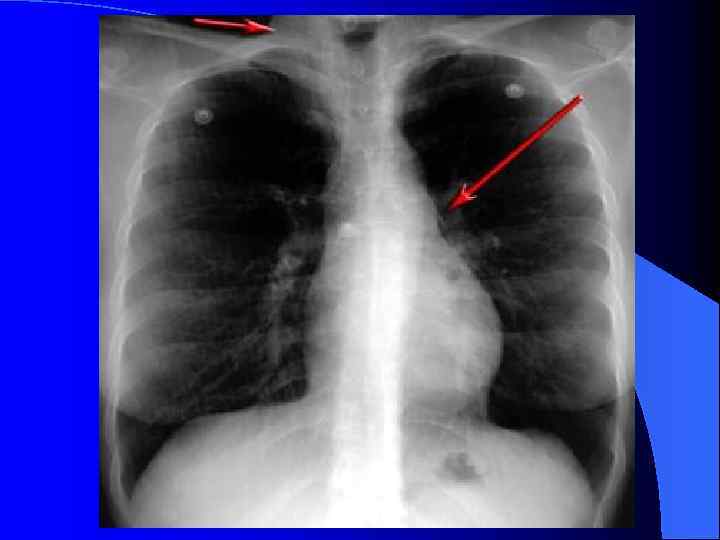

Клиника Особенности приступа: • приступ удушья, обычно ночью или утром; • одышка экспираторная, удлинен затрудненый выдох, сухие свистящие хрипы, часто дистанционные – на расстоянии, >>ЧД; • эквивалентами приступа удушья – приступы спастического сухого кашля, с затрудненым выдохом; • симетрическое вздутие грудной клетки; • положение ортопноэ (фиксация плечевого пояса);

Клиника Особенности приступа: втяжение межреберий; • выбухание над- и подключичных ямок; • перкуторно - коробочный звук, • аускультативно - ослабление дыхания с удлиненным выдихом, диффузные рассеяные сухие свистящие хрипы на выдохе; • у детей раннего возраста - разнокалиберные влажные хрипы на вдохе; • тахикардия, повышено АД, боли в животе, рвота;

l l l l Обструктивная ДН характерна для хронического бронхита. Она характеризуется одышкой с затруднённым выдохом. При осмотре больного отмечаются следующие признаки обструктивной ДН: бледность кожи или её сероватый оттенок (из-за диффузного цианоза), удлинение выдоха, участие в дыхании вспомогательных мышц, признаки значительных колебаний внутригрудного давления[1], увеличение грудной клетки в переднезаднем размере.